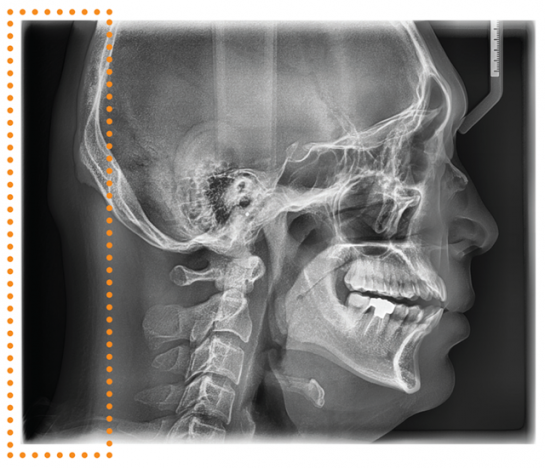

CEPHALOMETRIC (SCAN CEPH)

The PaX-i provides optimal images exclusively designed for orthodontics.

There are two image sizes available, Lateral and Full Lateral, allowing you to choose your image size based on your diagnostic needs.

CEPHALOMETRIC (SCAN CEPH)

The PaX-i provides optimal images exclusively designed for orthodontics.

There are two image sizes available, Lateral and Full Lateral, allowing you to choose your image size based on your diagnostic needs.

LATERAL

Provides specialized high quality images to suit orthodontics and maxillofacial surgeries

FULL LATERAL

A full lateral image size is 30% wider and shows the occipital area of the patient, which enables comprehensive diagnosis.

LATERAL

Provides specialized high quality images to suit orthodontics and maxillofacial surgeries

FULL LATERAL

A full lateral image size is 30% wider and shows the occipital area of the patient, which enables comprehensive diagnosis.